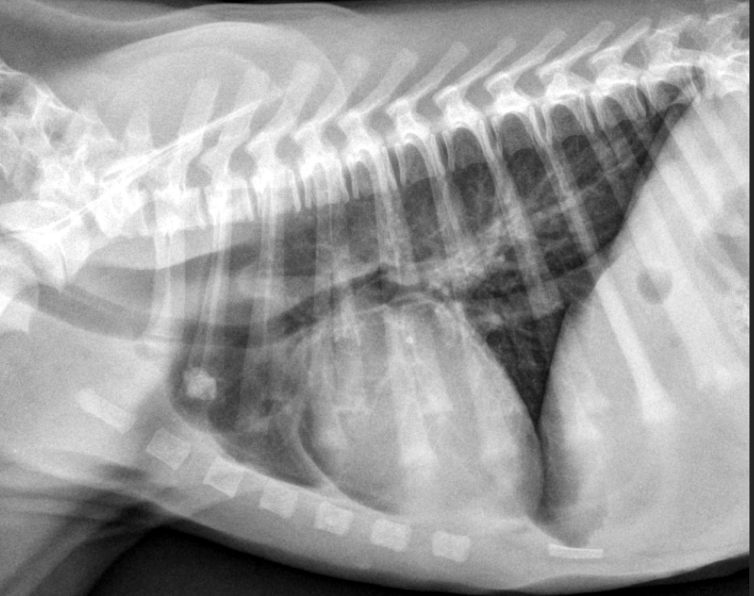

12

Esophageal dilation